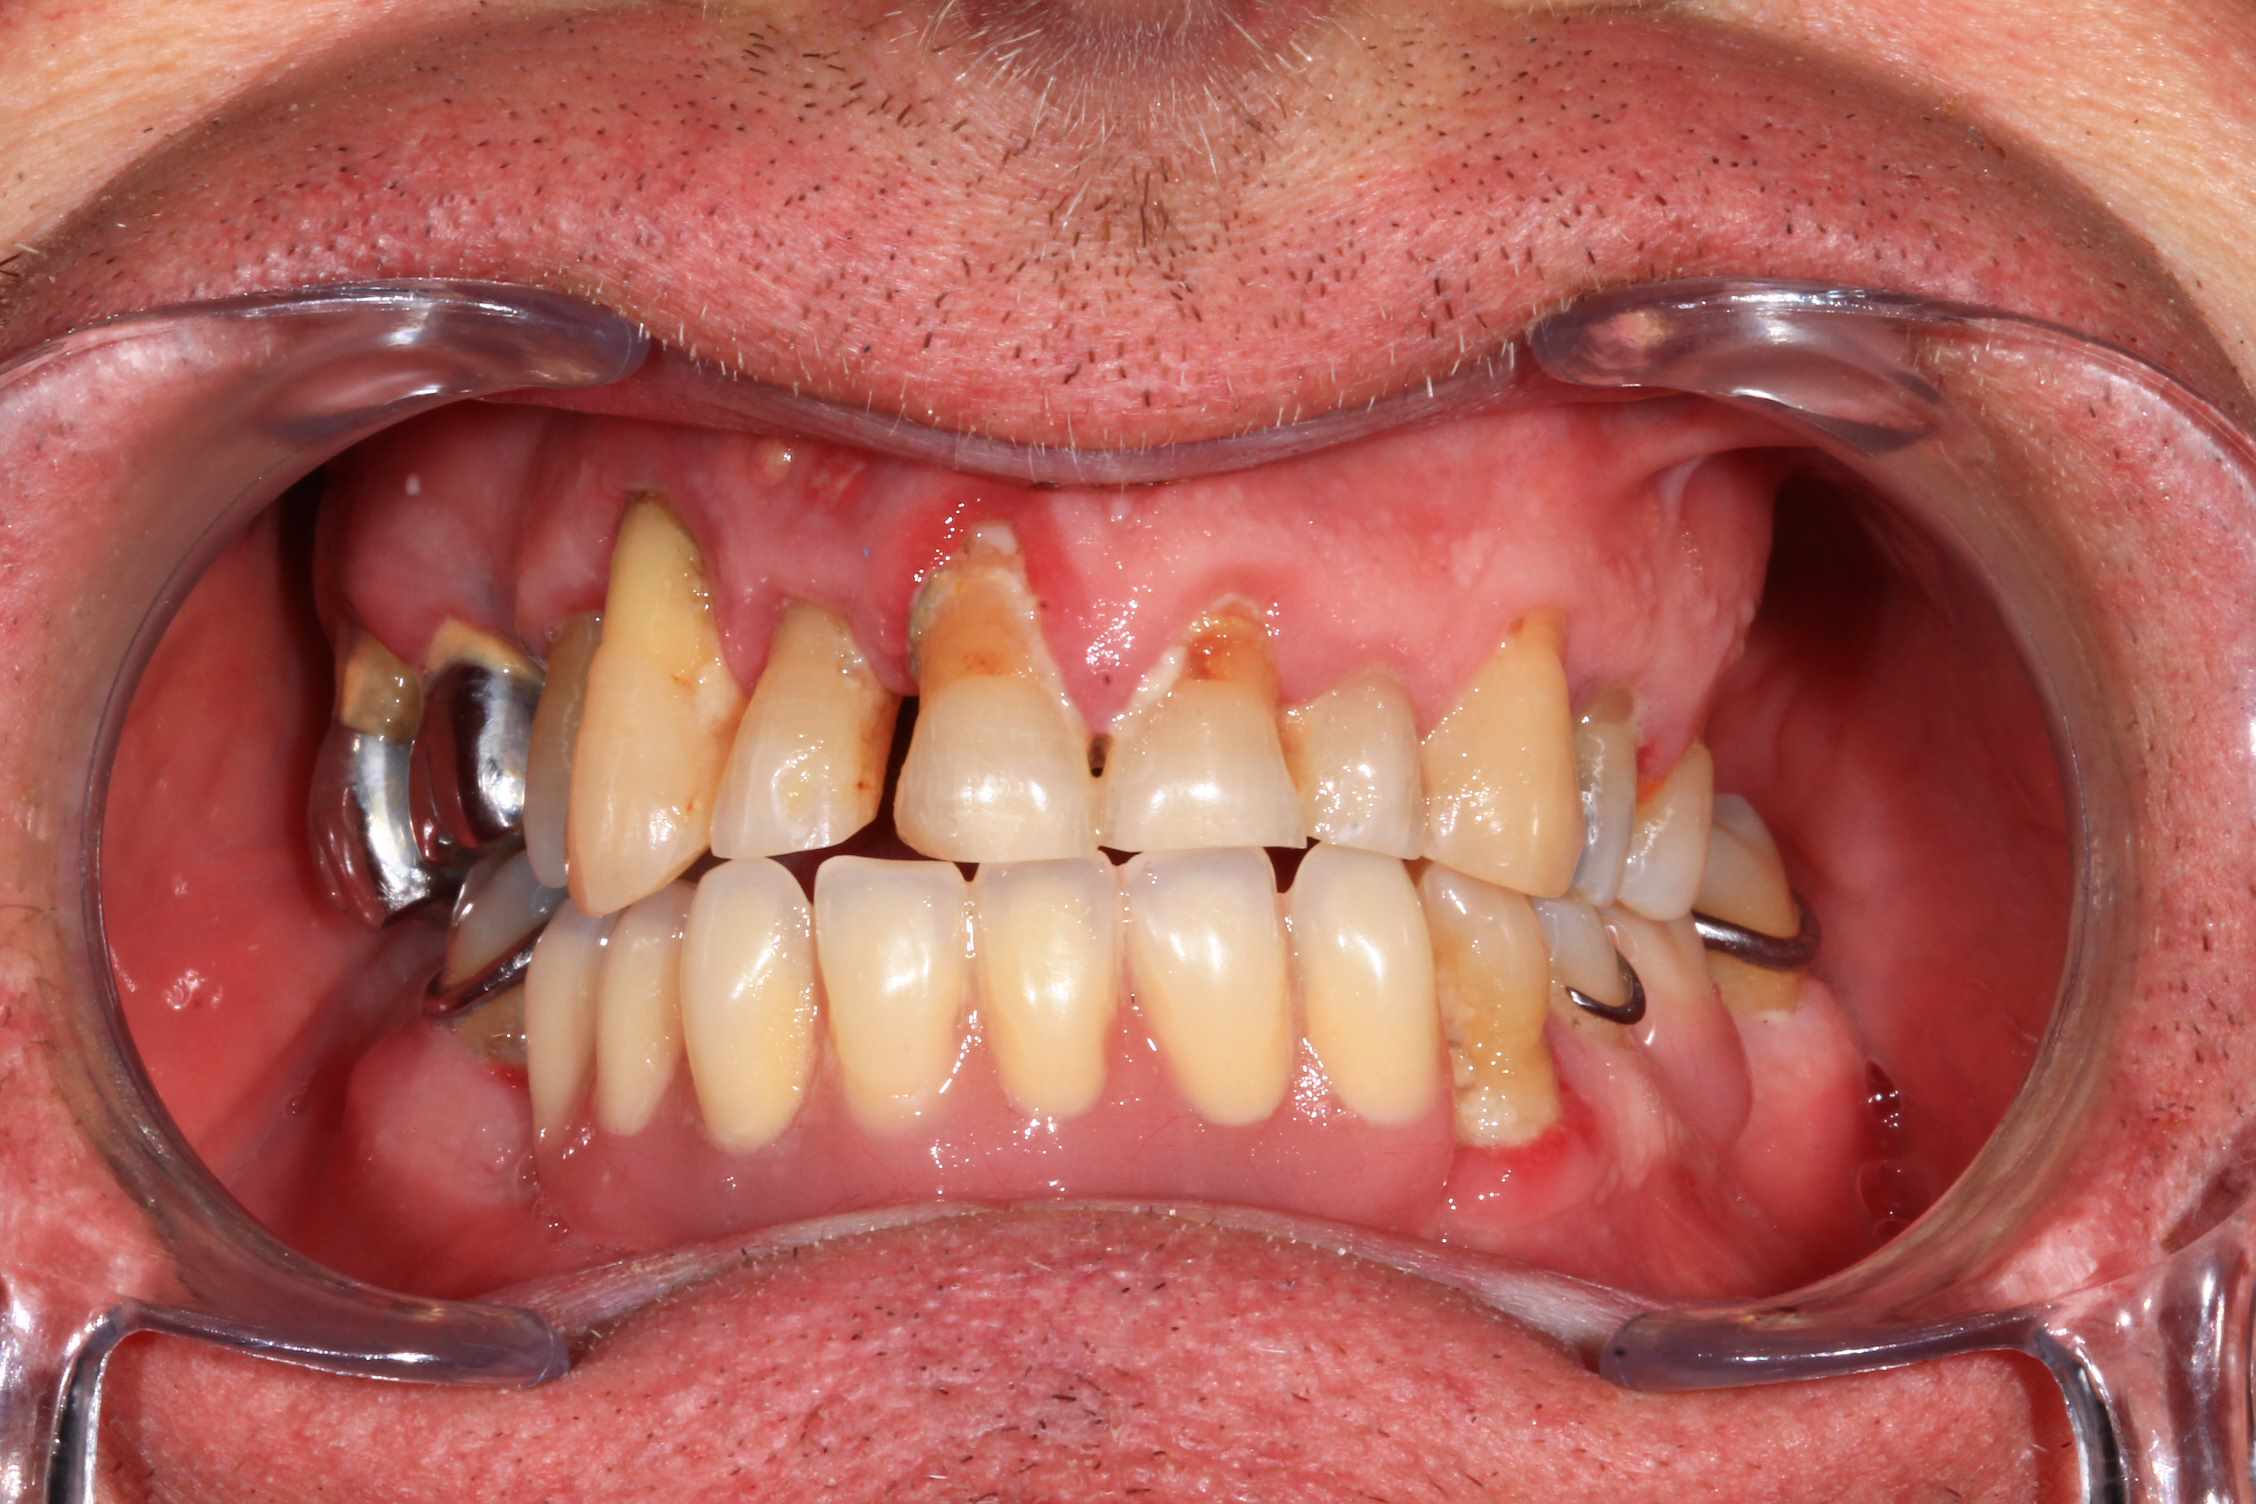

Cas 1 : patient ayant une 23 fracturée, avec 11 21 22 en mobilité terminale.

Planification des extractions, pose de 3 implants et mise en esthetique instantanée.

:) . effectivement terrain paro chronique, déjà traité il y a quelques année a paris. Plus ou moins stabilisé, pas de saignement, un peu de tartre en bas. des mobilités importantes sur les incisives antérieures qui, avec la facture de la 23 ont emporté ma décision. Solution alternative : stellite ? dans un an, tu extrais les dents support de crohet. Bridge ? cela me semble plutôt casse gueule.

Donc, implant , sur un terrain qui n'est pas idéal, certes, mais c'est souvent le cas.